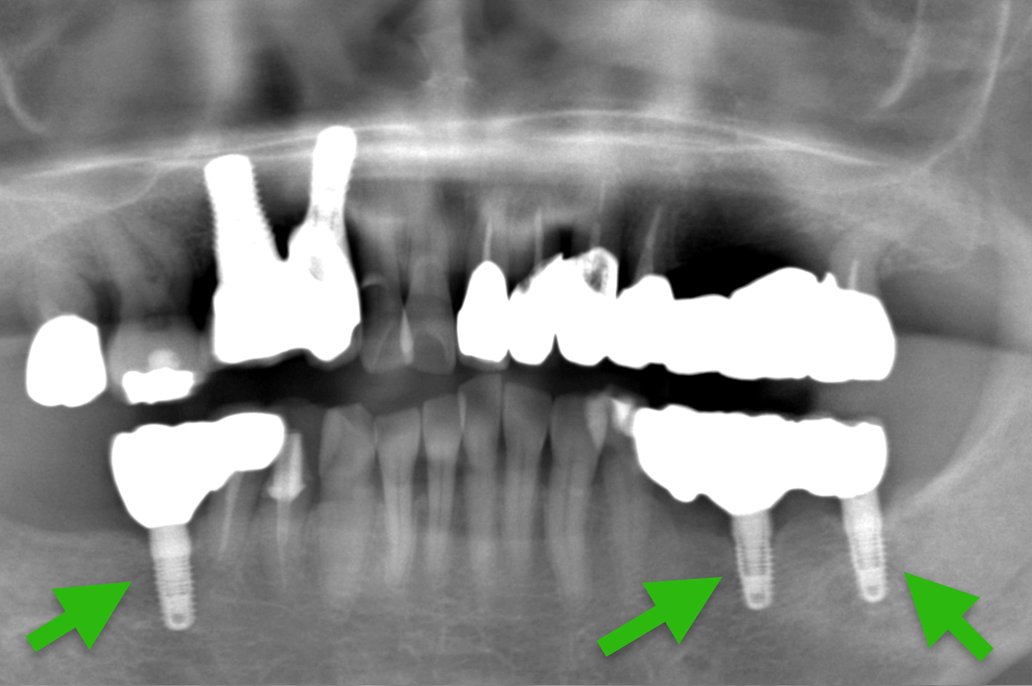

Case1.

| 主 訴 | 30年前に治療した部分が心配、 全て綺麗に新しくしたい |

| 治療期間 | 約1年 |

| 治療費 | インプラント2本、 オールセラミッククラウン12本 2,420,000円(税込) |

| 治療内容 | 右上の奥歯2本をインプラントで治療を行いました。 残りの古い被せ物を全て除去し仮歯を作成、 その後セラミックの型取りを行い、 セラミックをセットしました。 |

| 治療のリスク | 仮歯の間は噛み合わせに違和感を感じる場合が あります。 セラミックは稀に欠ける場合があります。 |